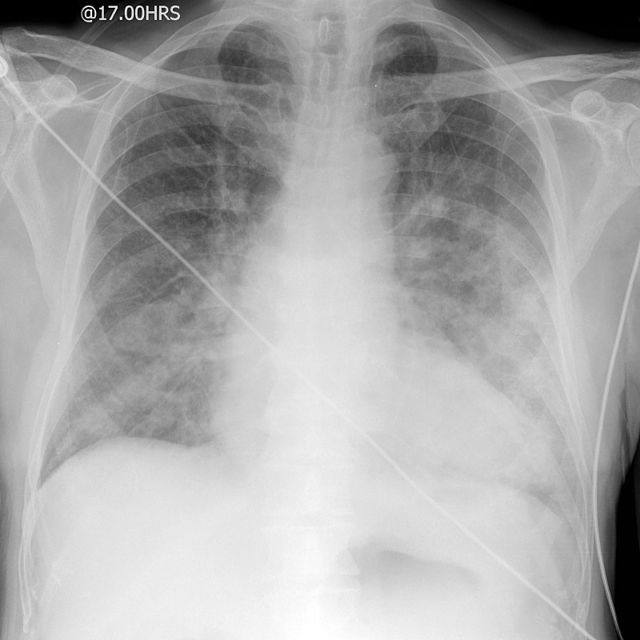

Take a look at the following example. Let us go through how we would systematically analyse this and the diagnosis.

D – This is a Chest X-Ray taken on ….., of the following patient….. Is there a previous CXR to compare to

R – Commenting first on the quality, it is not rotated, there is adequate inspiration, the projection is posterior-anterior and it is adequately exposed as I can see the vertebral bodies clearly

“On initial inspection, there appears to be increased opacification in the right middle lobe, but I will proceed to go through it systematically.”

A – Starting with the airways, the trachea is not deviated, and the carina is visible.

B – The pleural markings go all the way to the costal margin so there is no evidence of a pneumothorax. Going through the lung zones, there is increased opacification in the right middle lobe compared to the left. This opacification does not follow the contours of a lobe and has well defined edges, suggesting that it may be a mass.

C – The heart is not enlarged and the borders are visible.

D – The hemidiaphragms are clearly visible and there is no blunting of the costophrenic angles. There is no free air under the diaphragm.

E – There are no foreign objects or bone fractures.

There is no abnormality in the review areas, including the apices, behind the heart

In summary the key finding is an opacification in the left hilar region, which is suggestive of a mass.

Diagnosis

Lung Cancer